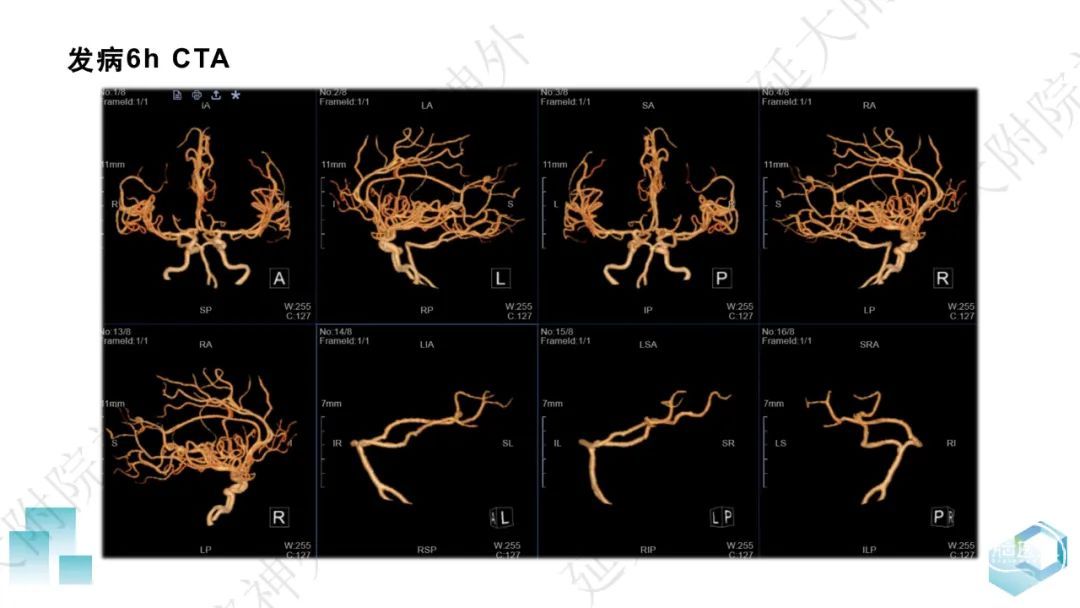

今天为大家分享的是《监测有道丨颅脑创伤-神经重症周刊》第332期,由延安大学附属医院神经外科贾云峰主任医师带来的:左侧基底节区出血破入脑室一例神经内镜下血肿清除术,欢迎阅读、分享。